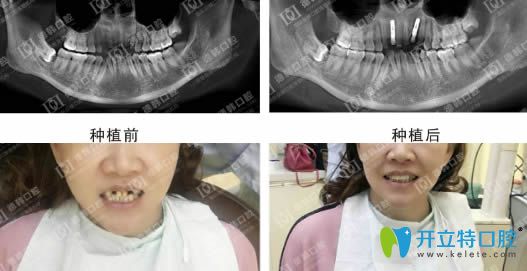

說一千,道一萬,武漢德韓種植牙到底怎么樣,不如效果展示來的實(shí)在:

德韓口腔種植牙效果前后對(duì)比圖